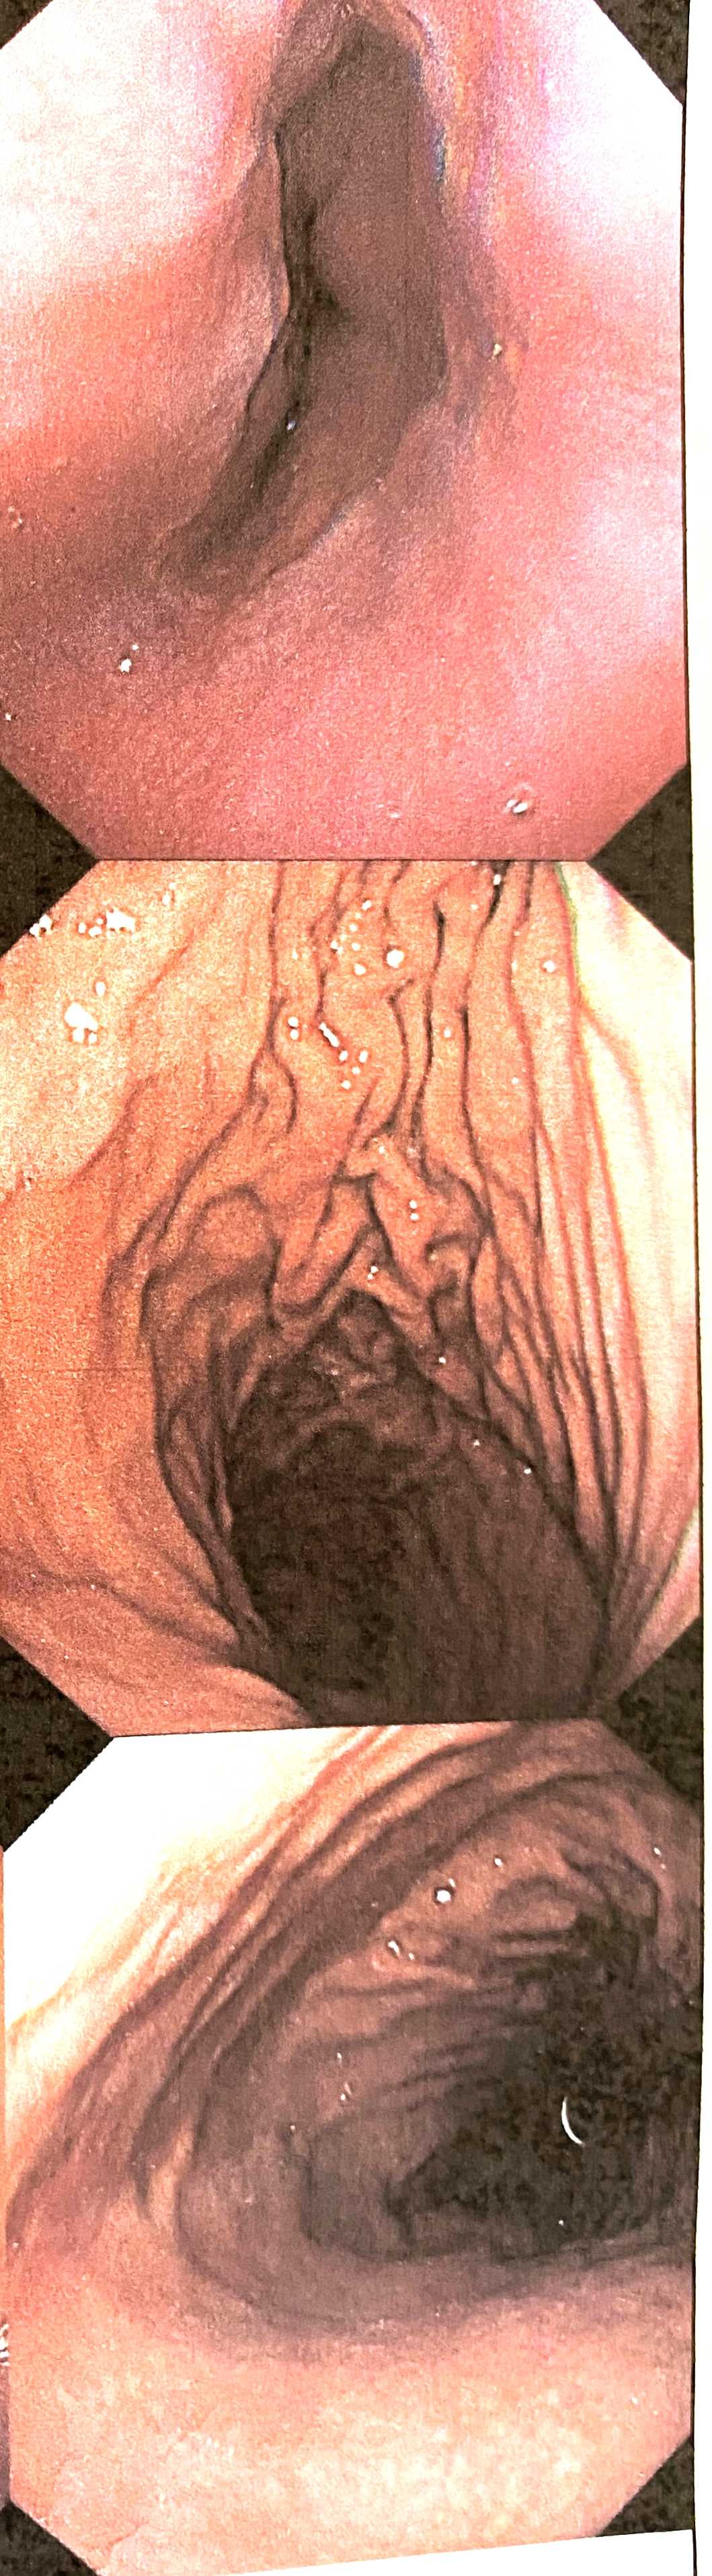

検査の結果、

画像はちょっと生々しいけど、

まず1枚目。

赤く線状になっている部分は、胃炎らしい。

私の場合は、胃潰瘍までにはなってなくて、

おそらく慢性的な胃炎らしい。

そして、

2枚目と3枚目。

胃の粘膜が、

しわが有るところと、無いところがあるでしょ。

胃の粘膜って、

若いとしわが多いんだって。

つまり、

しわが無いところは、粘膜が老化してるってこと。

これ、

顔とは真逆だよなあ。

若いほどしわしわ。